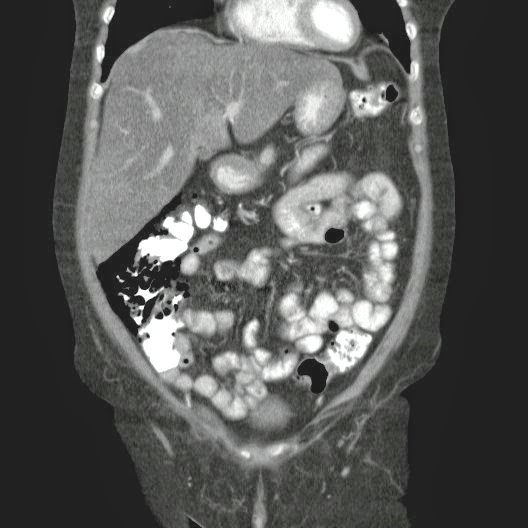

- ¿Hallazgos Escanografia?

2. Hay una colección de la pared abdominal en el flanco derecho, que realza en la periferia con el contraste, e intraabdominal tiene aire pero no me parece colección intraabdominal porque la grasa no está alterada.